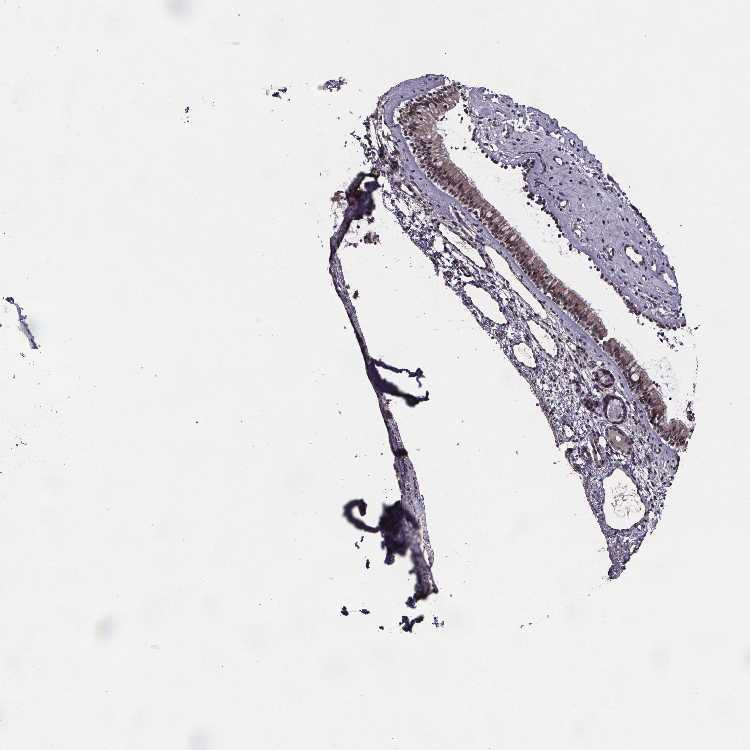

NASOPHARYNX - Antibody stainingi

Antibody staining in the annotated cell types in the current human tissue is reported as not detected, low, medium, or high, based on conventional immunohistochemistry profiling in selected tissues. This score is based on the combination of the staining intensity and fraction of stained cells.

Each image is clickable and will lead to virtual microscopy that enables deeper exploration of all samples and also displays staining intensity scores, fraction scores and subcellular localization as well as patient and tissue information for each sample.

Antibody HPA065831

Respiratory epithelial cells Medium